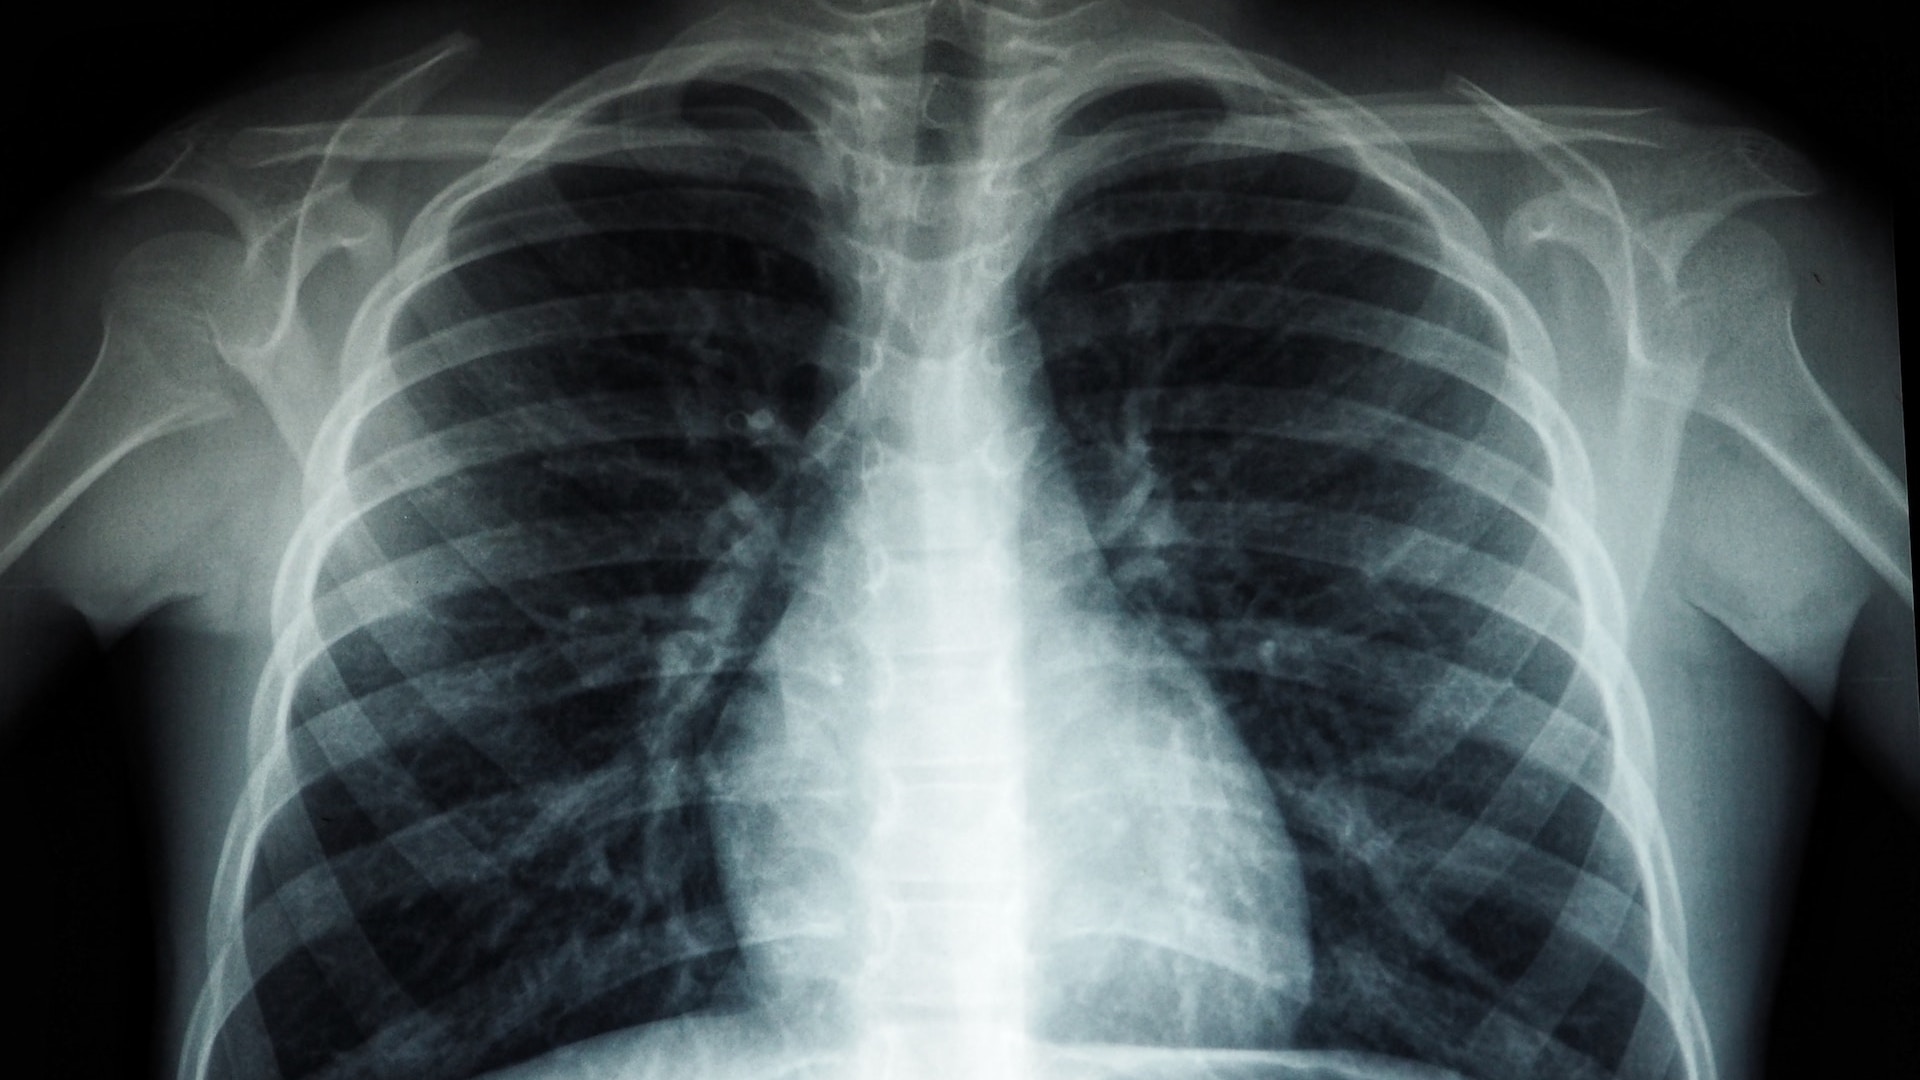

Ученые из Осакского столичного университета разработали модель искусственного интеллекта, способную определять биологический возраст людей по рентгеновским снимкам грудной клетки. Об этом сообщает Bizmedia.kz.

Эксперты из университета Осака обучили искусственный интеллект определять биологический возраст человека на основании рентгеновских снимков грудной клетки. Ведущий медицинский журнал The Lancet Healthy Longevity опубликовал результаты данного исследования.

Впервые в медицинской практике была создана модель ИИ, использующая глубинное обучение для оценки возраста через рентген грудной клетки. Для дизайна, обучения и проверки алгоритма с 2008 по 2021 год была создана база из 67 099 рентгеновских снимков от 36 051 здорового индивидуума из трех различных медицинских учреждений.

После этого модель была протестирована на рентгенограммах пациентов, страдающих от разнообразных заболеваний. Дополнительными материалами для тестирования послужили рентгеновские снимки грудной клетки 34 197 пациентов с гипертонией, метаболическими нарушениями и хроническим обструктивным заболеванием легких.

Изучение показало, что ИИ часто указывает на более старый возраст у пациентов с различными заболеваниями.

«Наше исследование демонстрирует, что расчетный возраст, основанный на рентгеновской графии грудной клетки, может быть точным индикатором состояния здоровья пациента», — подчеркивают ученые.

Этот прорыв в исследованиях может стать основой для создания новых инструментов, способных оценивать степень хронических заболеваний, предсказывать ожидаемую продолжительность жизни, а также вероятность хирургических осложнений.